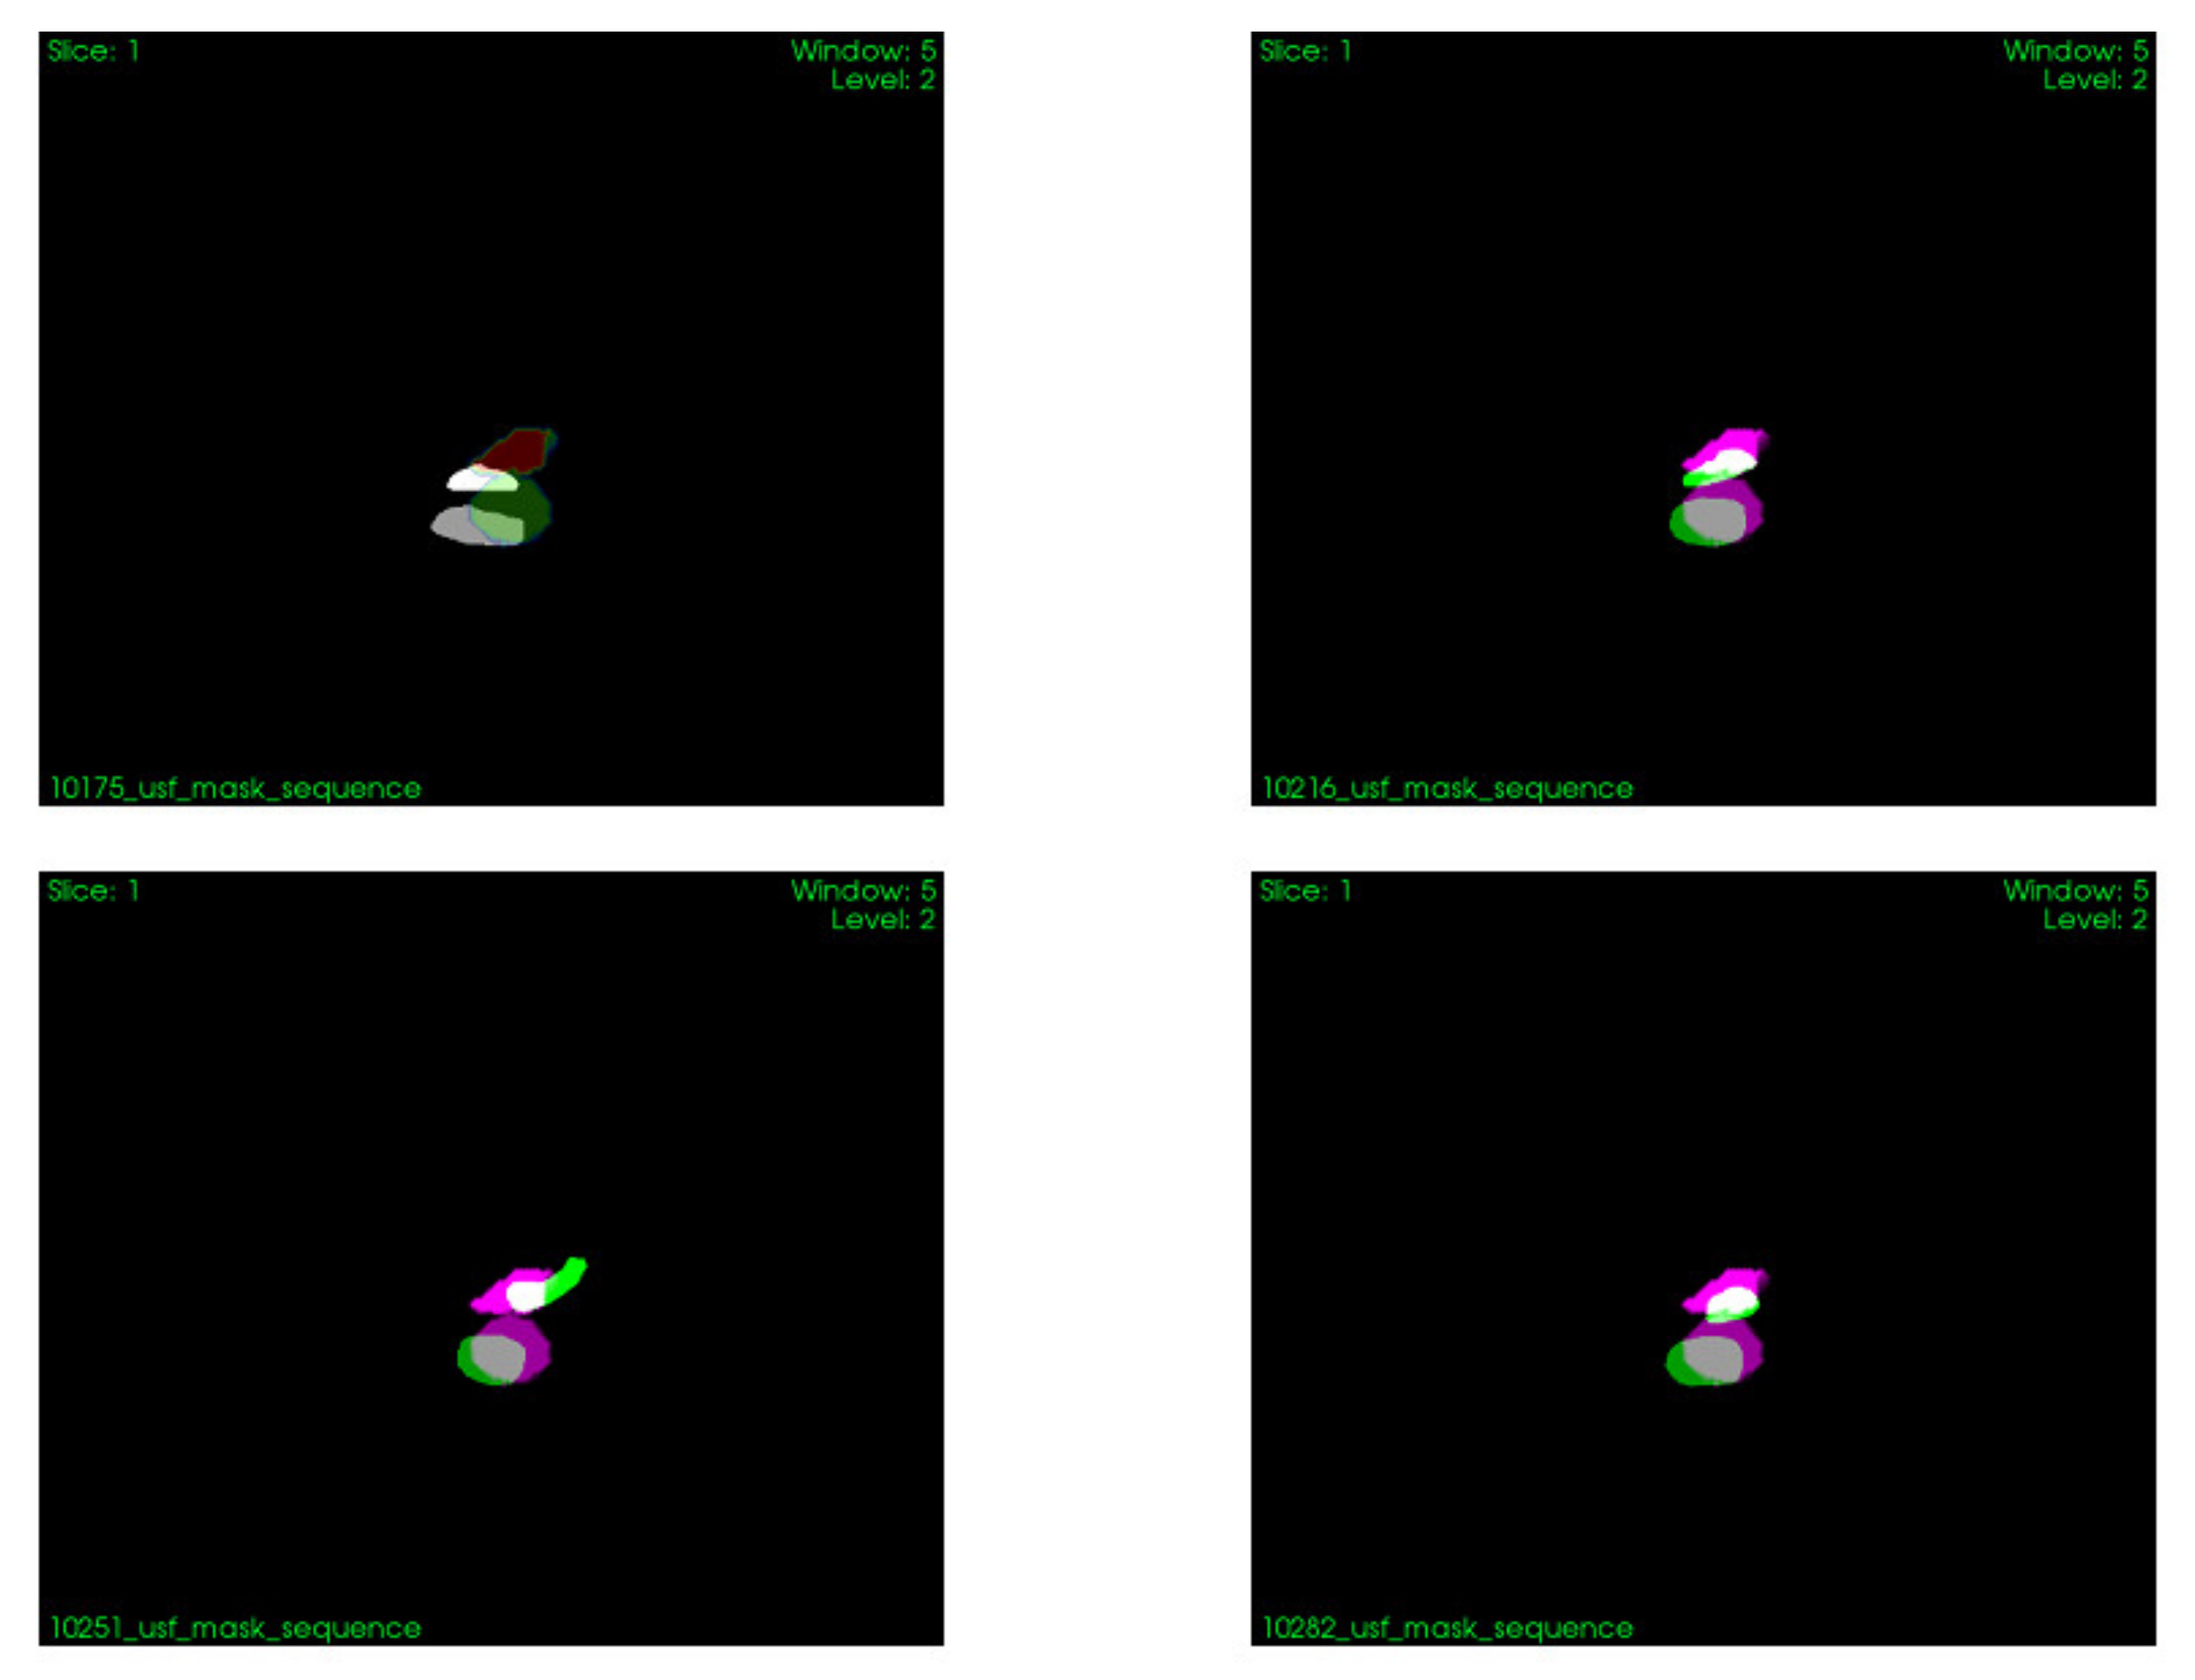

2.2.4. Validation Method

3.2. Synchronization of Information from Pre-Operative and Intraoperative Images